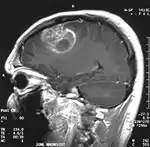

Глиобластома

Мультиформная глиобластóма (англ. Glioblastoma multiforme, GBM) — наиболее частая и наиболее агрессивная форма опухоли мозга, которая составляет до 52 % первичных опухолей мозга и до 20 % всех внутричерепных опухолей. Несмотря на то что глиобластома является наиболее частой первичной опухолью мозга, на 100 000 жителей Европы и Северной Америки регистрируется всего 2—3 случая заболевания[1]. Термин «глиобластома» подразумевает два варианта этой болезни: гигантоклеточная глиобластома и глиосаркома.